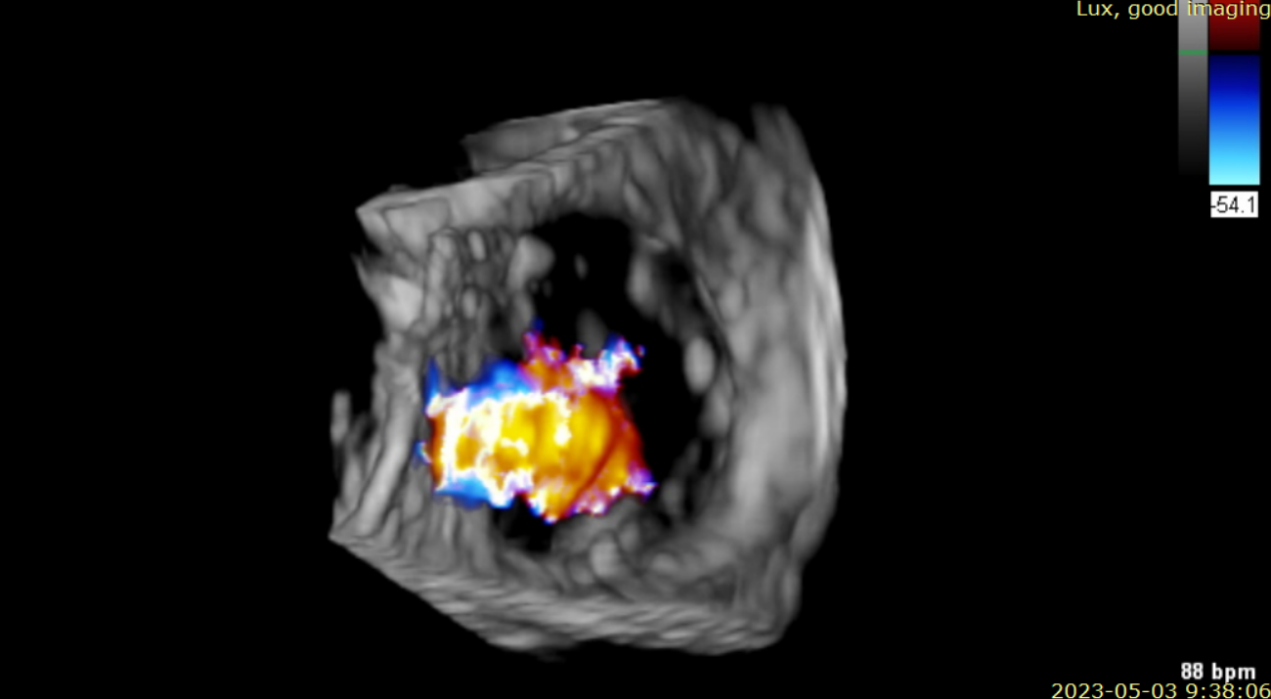

術前超聲提示大量三尖瓣反流

術中輸送器在超聲引導下調整位置